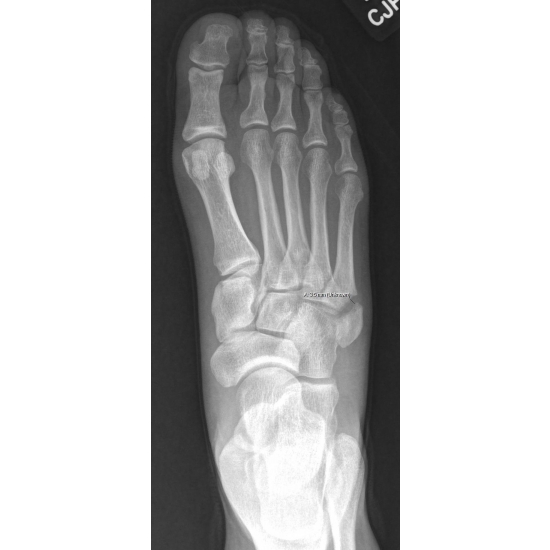

She continued with protected weight bearing in a walking boot and was later placed in a non-weight bearing cast for 4 weeks because of increasing diastasis of her fracture pieces. Case Photo #3 Case Photo #4